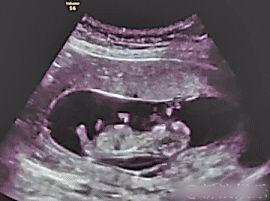

B超,全称超声波检查,是一种无创的医学检查方法。通过B超,医生可以观察到胎儿在母体内的生长情况,包括胎心、胎动、羊水等。而B超视频,则是将这一过程以动态的形式呈现出来,让准妈妈和准爸爸们能够亲眼见证宝宝的成长。

1. 胚胎阶段:在这个阶段,宝宝还只是一个小小的胚胎,但B超视频已经能够清晰地看到他的心跳和轮廓了。这个时候的宝宝,就像是一个小小的探险家,在妈妈的肚子里探索着这个未知的世界。

2. 胎儿阶段:随着宝宝的成长,B超视频中的画面也越来越丰富。这个时候,我们可以看到宝宝的小手、小脚,甚至还能看到他吞咽羊水的样子。这个时候的宝宝,已经能够感受到妈妈的爱了。